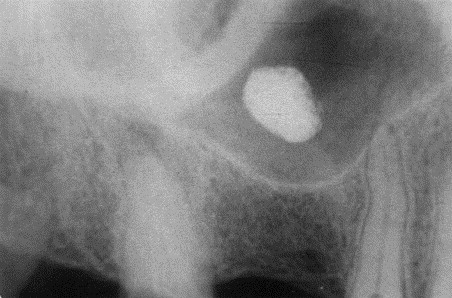

3. What condition can be seen in the following X ray?